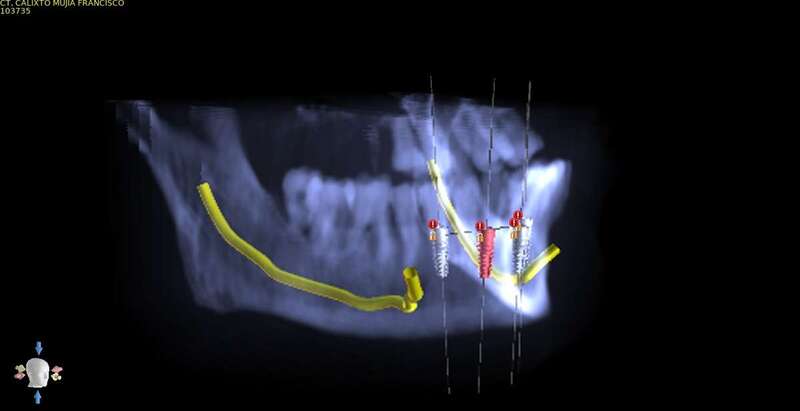

Cirugía guíada por ordenador

El doctor Juan Carlos Rodríguez Pascuas especialista en cirugía de la clínica explica a continuación como funciona y en qué consiste el sistema de cirugía guiado por ordenador:

-Existe un gran abanico de posibilidades para reponer los dientes perdidos con implantes, desde la colocación de unos pocos implantes para reponer todos los dientes, hasta la colocación de implantes y dientes provisionales en el mismo día. Nuestra intención es ofrecer a cada paciente lo que mejor se adapte a su situación. Para ello aprovechamos las últimas tecnologías disponibles, como la Cirugía Guiada por ordenador. Así, el paciente puede ver previamente las opciones que tiene y decidir qué tipo de tratamiento prefiere.

-No tiene por qué serlo. Con los avances tecnológicos que tenemos a disposición, podemos hacer cirugías mínimamente invasivas guiadas por ordenador, que en muchos casos no necesitan ni siquiera puntos de sutura. Durante el tratamiento el paciente no siente ningún dolor y con la adecuada ayuda farmacológica y unos pocos cuidados, en la gran mayoría de los casos no hay ni molestias ni inflamación después de la cirugía.